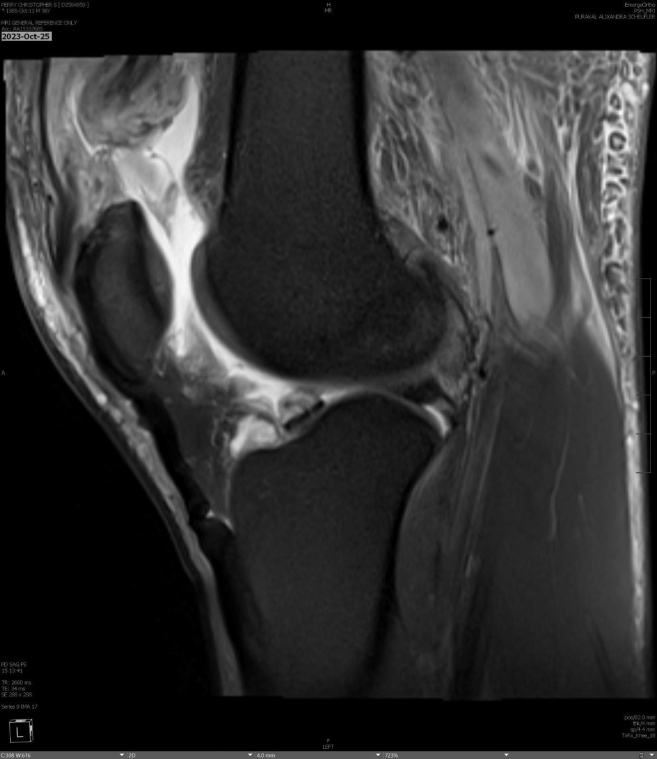

Abstract Image